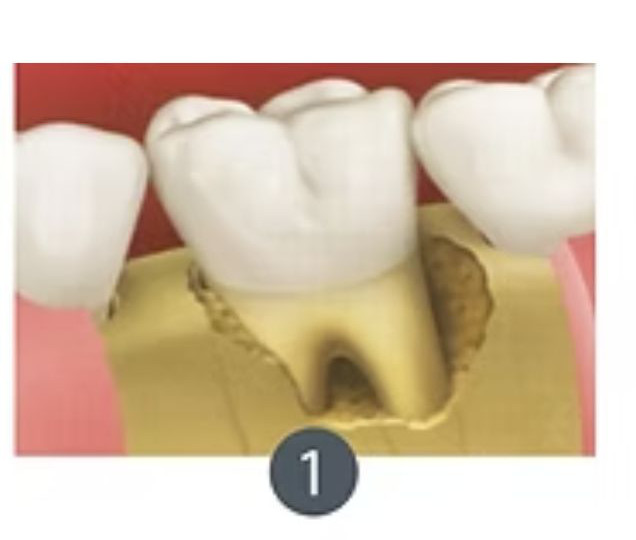

Exodoncia+ Preservación de alvéolo

La exodoncia con preservación del alveolo es un procedimiento dental que combina la extracción de un diente con la protección y preservación del alvéolo dental (la cavidad en el hueso donde estaba el diente) para facilitar futuras restauraciones dentales, como la colocación de implantes dentales.